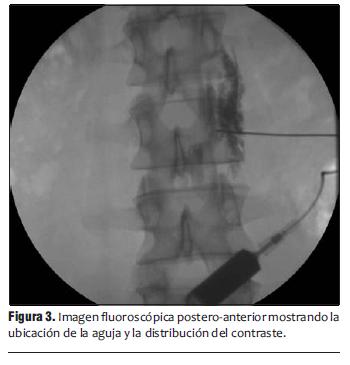

Se inyectó contraste no iónico (Iopamidol 300 mg/ml) 0,5-1 ml, observando en tiempo real su difusión en forma de línea compacta en el borde vertebral anterior por delante del músculo psoas bajo visión lateral (figura 2) y su característica distribución en visión postero-anterior (figura 3).